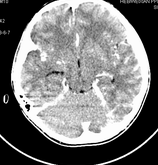

男,10岁,因近来常头痛就诊。先平扫拟诊右侧脉络膜裂囊肿,后薄层(3mm)扫描见此灶与右侧脑室后角相通,且向内几乎与鞍上池相连,并见一血管影沿其走形 (可能是脉络膜前动脉)。1。请教:脉络膜裂或脉络膜裂囊肿与侧脑室颞角或鞍上池相通吗?好像谁说脉络膜裂是脉络膜从外侧裂向侧脑室移行的裂隙。请高手讲讲这点的解剖关系。2。建议:对于老年患者,有丘脑附近特别是右丘脑附近的近似腔隙性梗死灶,临床症状不明显的,应做3mm薄层扫描,看病灶向下是否与侧脑室颞角相连,以免误诊。

薄层强化: